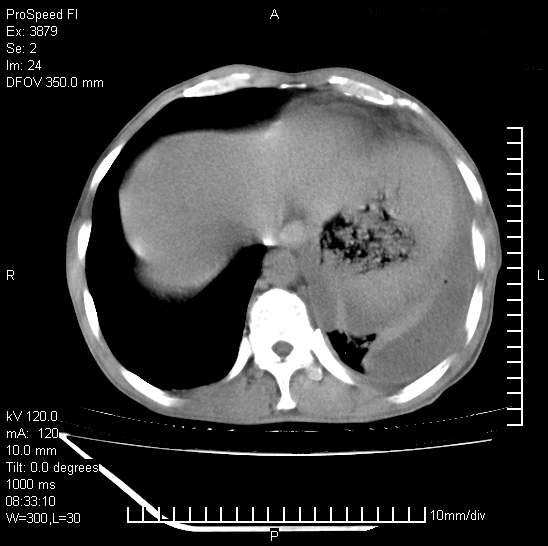

以下是引用37度在2008-6-6 11:20:00的发言:[br]1.包裹性积液,多考虑结核性;[br]2.穿刺术后改变。